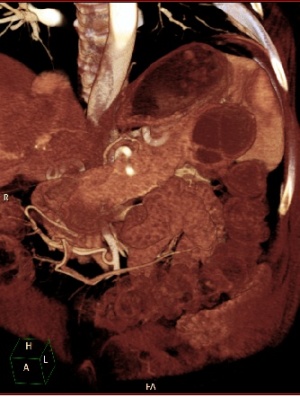

- טומוגרפיה ממוחשבת - הבדיקה השנייה בחשיבותה מאפשרת הדגמה של השאת ומיקומה (תצלום 18.9).

| תצלום 18.9: מימין -כיסית אמיתית בזנב הלבלב החצים מצביעים על גבולות הכיסית. משמאל - טומוגרפיה ממוחשבת מראה כיסית מדומה (פסוידוציסטה) מרכזית מדממת. | |